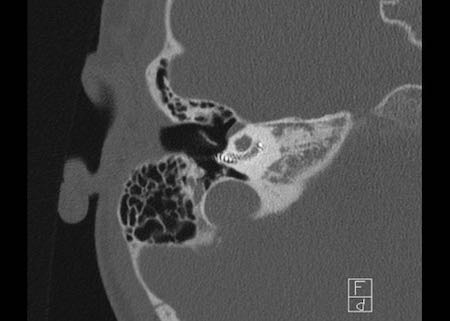

Bên trái là hình ảnh của một bé gái 2 tuổi.

Các hình ảnh từ kết quả chụp CT được thực hiện trước khi cấy ốc tai điện tử.

Quan sát thấy dị dạng nhẹ ở đỉnh ốc tai – không có sự phân tách giữa vòng thứ hai và vòng thứ ba, và trụ ốc tai xương vắng mặt.

Cống tiền đình bình thường.